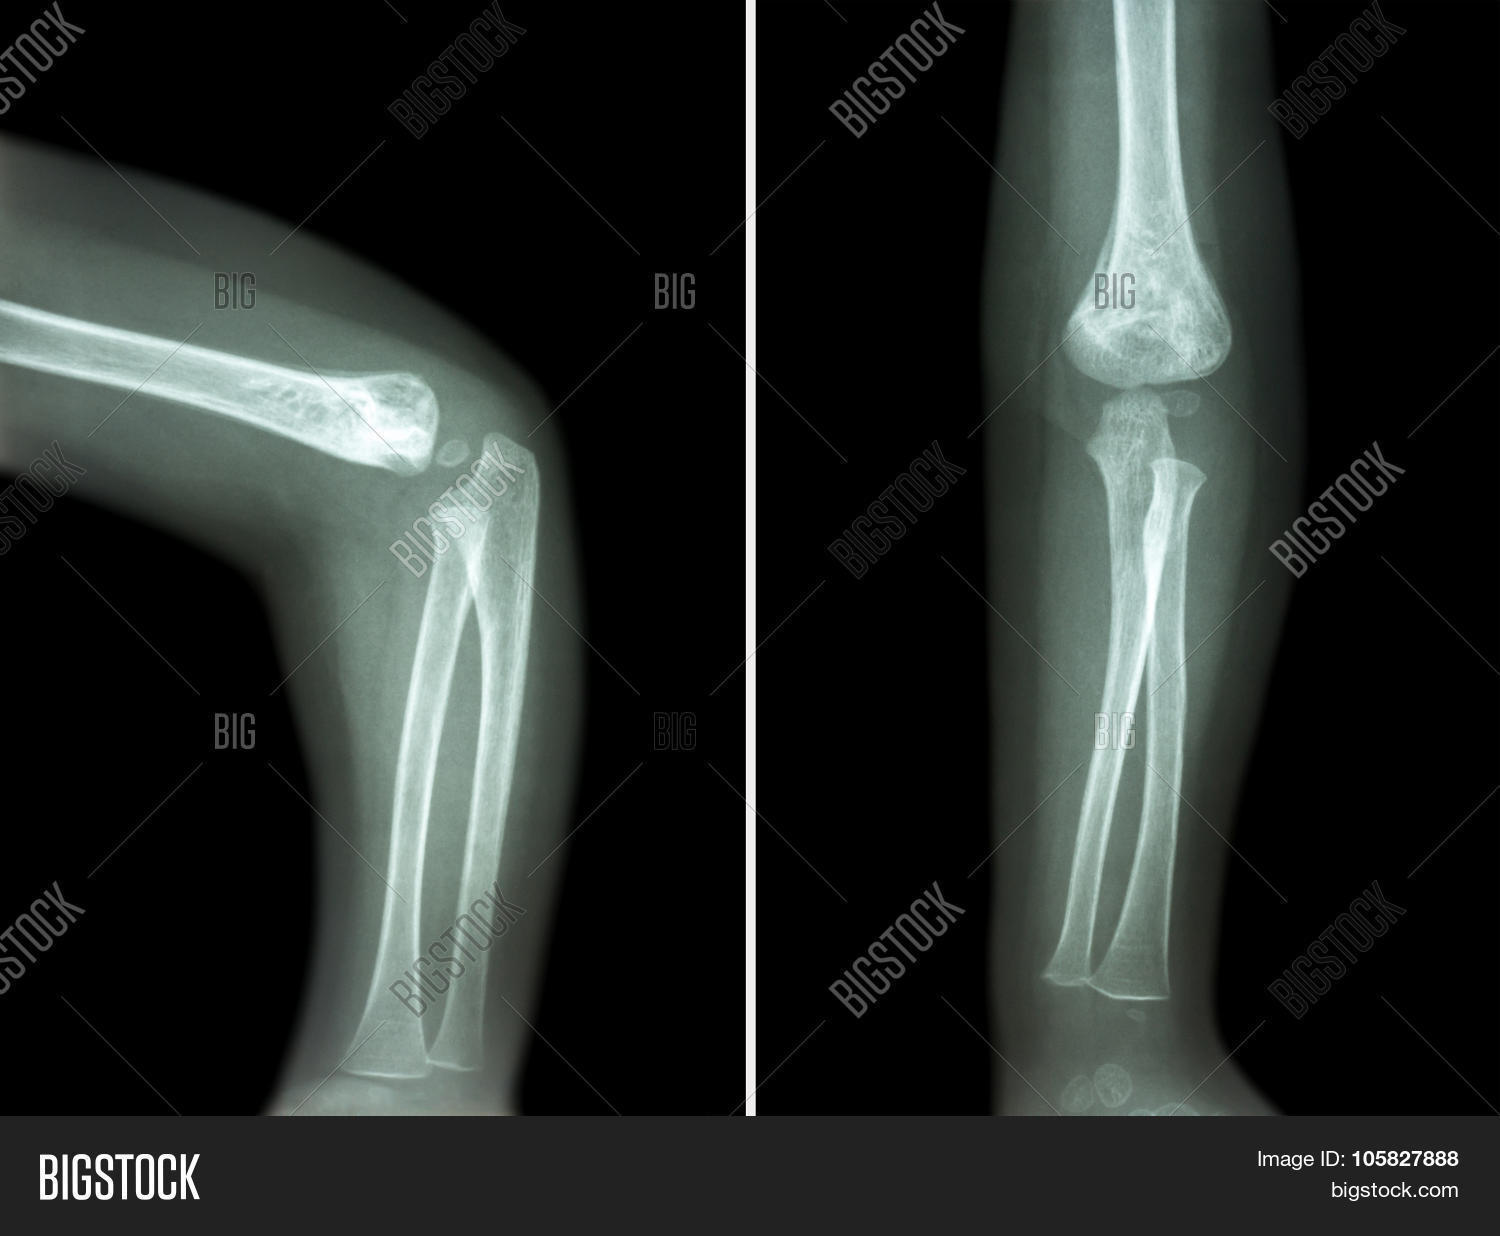

Left Elbow X-Ray Film . In adults, elbow dislocation is the second most common. Web the elbow series is a set of radiographs taken to investigate elbow joint pathology, often in the context of trauma.

Fractures lines can be difficult to visualize after acute elbow injury, particularly in children. The osseous anatomy of the elbow is complex, and fractures can occasionally be radiographically occult or. Web this view is clinically indicated for trauma to, chronic discomfort or infection of the elbow joint.

Web this view is clinically indicated for trauma to, chronic discomfort or infection of the elbow joint. It aids in visualizing fractures and/or. Web elbow fractures and dislocations are commonly seen in the acute care setting. Fractures lines can be difficult to visualize after acute elbow injury, particularly in children.